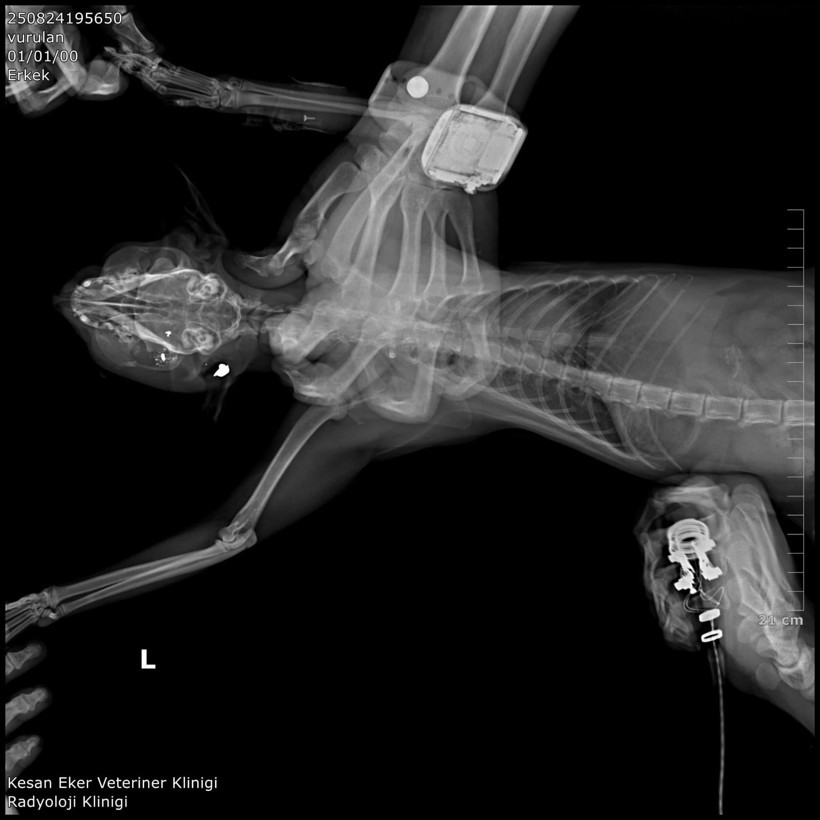

Klinik raporunda, 'ateşli silah yaralanması ile uyumlu patolojiler' tespit edildiği, hayvanların tüfek saçması sonucu öldüğüne ilişkin bulgulara yer verildi. Bülbül, güvenlik kamerası görüntülerinden komşusu K.G.'den şüphelendi. Görüntülerde; K.G.'nin bahçesine giren bazı kedilerin aniden kaçtığını fark etti.

K.G.'nin kedileri bahçesinde ateşli silah ile vurduğunu belirten Ürkmez, "Bununla ilgili delillerimizi dosyayla sunmuş bulunmaktayız. Onun haricinde veteriner ön raporunda da kedilerin ölümüyle ilgili olarak vücutlarında saçma bulunduğu açıklığa kavuşmuştur. Kamera kayıtlarımızı da delil olarak dosyayla sunduk. Bu konunun takipçisiyiz. '5199 sayılı Hayvan Haklarını Koruma Kanunu gereği de şüphelinin ceza alması için elimizden gelen her şeyi baro olarak yapmak niyetindeyiz. Bununla ilgili son kararı mahkeme verecektir. Şüphelinin yurt dışına çıkış yasağı ve adli kontrolü ise devam etmektedir" diye konuştu.